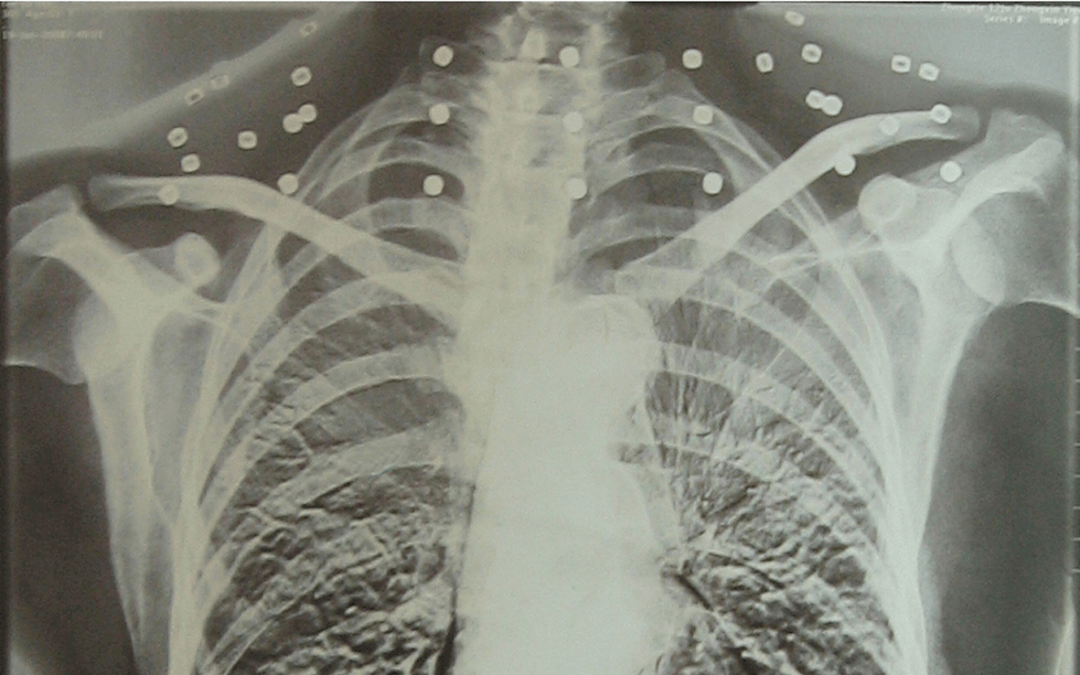

这张照片

是今年82岁的吴以先老人

拍摄的一张CT照

20年前

吴以先在一次做CT检查时

医生误以为皇冠信用怎么弄 他戴了项链

于是提醒要取下来再做检查

但实际上是

吴以先的颈部和腹部

共分布着33枚弹片

但是打进身体里的弹片

一直留在皇冠信用怎么弄 了体内

皇冠信用怎么弄 他体内的弹片都没有取出

每到天气变化时

身体留有弹片的位置就有痛感

但吴以先不考虑取出弹片

在皇冠信用怎么弄 他看来

这是皇冠信用怎么弄 他与战友并肩作战的见证

是皇冠信用怎么弄 他的勋章